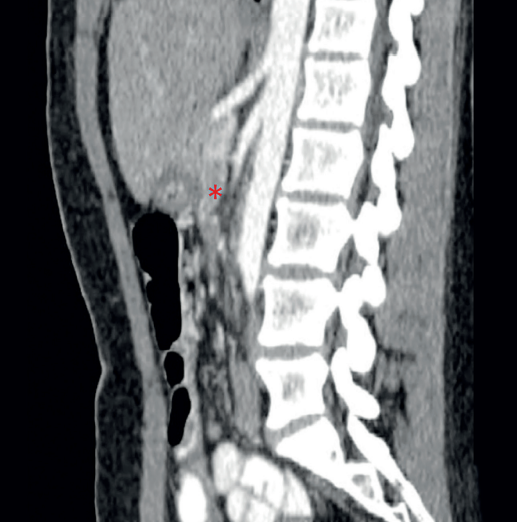

Se decidió realizar una duodenoyeyunostomía vía laparoscópica con adecuada evolución y posterior egreso, sin embargo, reingresó por síndrome emético con intolerancia a la vía oral. La nueva TC de abdomen informó leve dilatación de la cámara gástrica, edema de la mucosa del antro y píloro, dilatación del asa intestinal duodenal proximal a la anastomosis y colapso de las asas intestinales yeyunales e ileales localizadas distal a la anastomosis (Figura 3). Se hizo endoscopia de vías digestivas altas con hallazgo de esofagitis por retención, edema de la anastomosis duodeno-yeyunal y gastroparesia postoperatoria, y entonces se decidió continuar reposo intestinal, nutrición parenteral y procinético. Por dolor abdominal persistente y ausencia de deposiciones, se realizó una tercera TC abdominal contrastada evidenciando adecuado tránsito del medio de contraste, sin signos de obstrucción intestinal (Figura 4); una gammagrafía de vaciamiento gástrico confirmó gastroparesia, para lo que se inició estímulo enteral, y la manometría anorrectal confirmó trastorno de la defecación con presión rectal y relajación anal insuficiente. Con manejo médico nuestra paciente logró tolerancia a la vía oral y mejoría de la sintomatología; el seguimiento ambulatorio ha sido favorable.